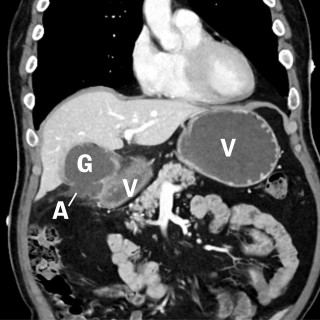

Kasuistikken beskriver en pasient med cystisk ekinokokkose og behov for omfattende kirurgisk behandling. Tilstanden er sjelden i Norge, men utgjør et betydelig folkehelseproblem globalt. På grunn av økende innvandring fra høyendemiske land, bør norske leger kjenne til denne zoonosen. En tidligere frisk mann i 40-årene, oppvokst i Midtøsten og bosatt i Norge de siste årene, ble akutt innlagt på medisinsk avdeling ved lokalsykehuset, etter to døgn med respirasjonsavhengige smerter i høyre hemitoraks. I forkant av innleggelsen hadde han hatt fem ukers sykehistorie med høyresidige flankesmerter...